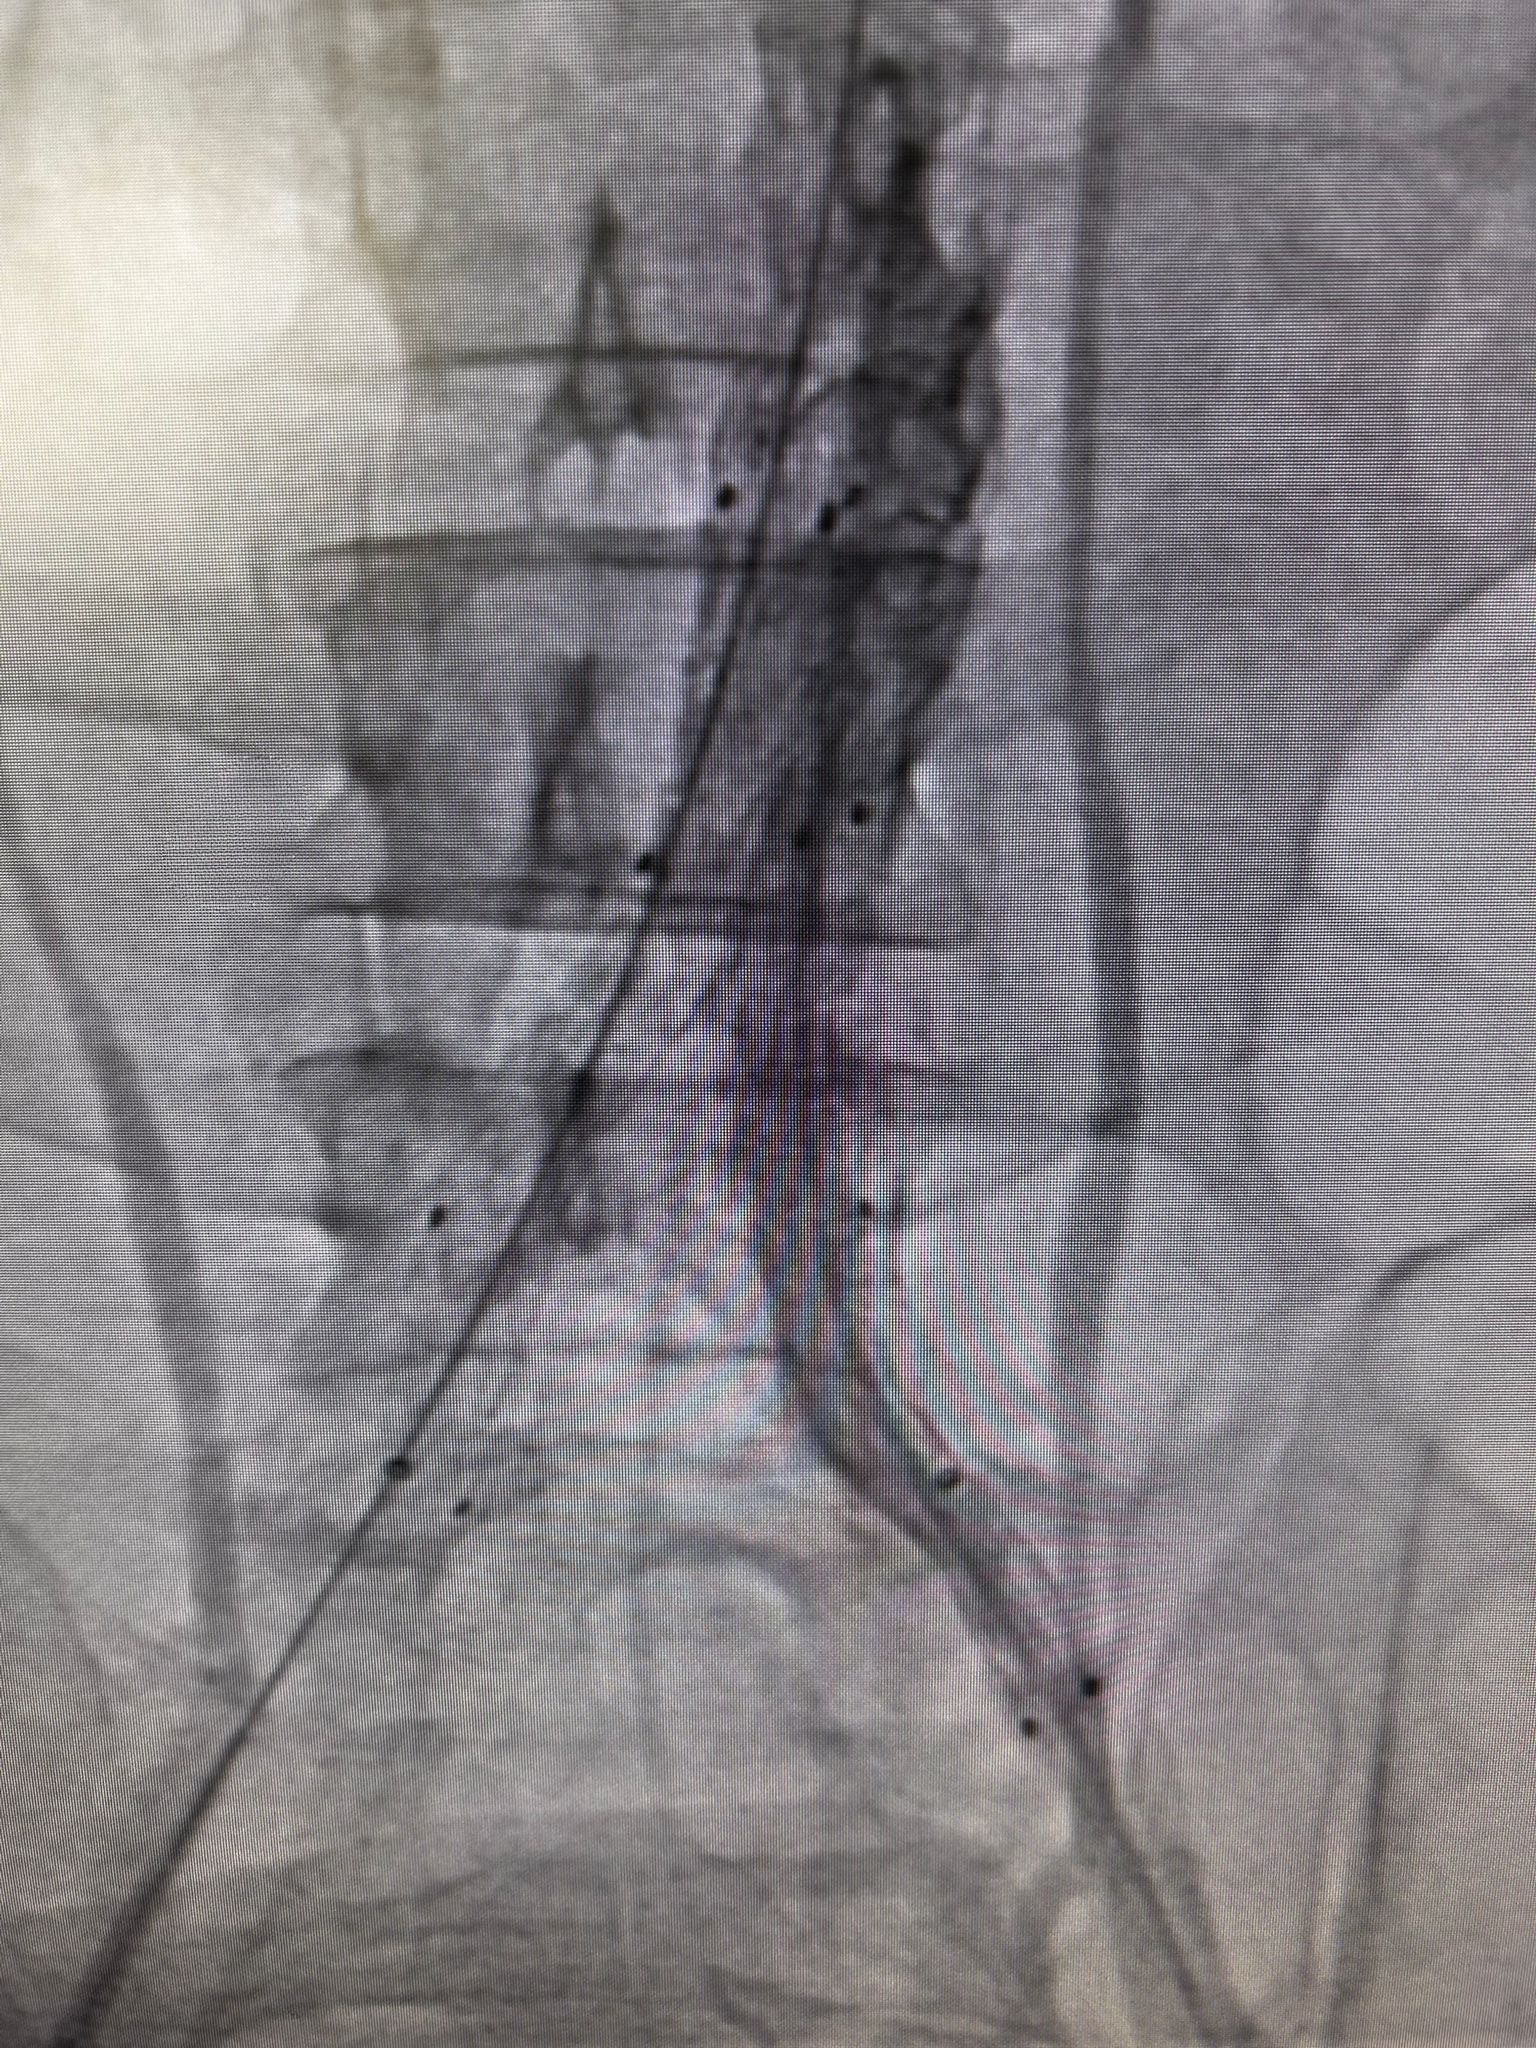

Damar içinden girilerek gerçekleştirilen işlem sırasında, yırtılan ana damarın içine özel bir stent yerleştirildi ve damar içten onarıldı. Açık ameliyata gerek kalmadan uygulanan bu yöntem sayesinde hasta kısa sürede rahatladı. Tedavi sonrası yakından takip edilen hastanın ağrılarının tamamen geçtiği, genel sağlık durumunun iyi olduğu gözlemlendi. Kontrollerinin sorunsuz seyretmesi üzerine hasta sağlıklı bir şekilde taburcu edildi.